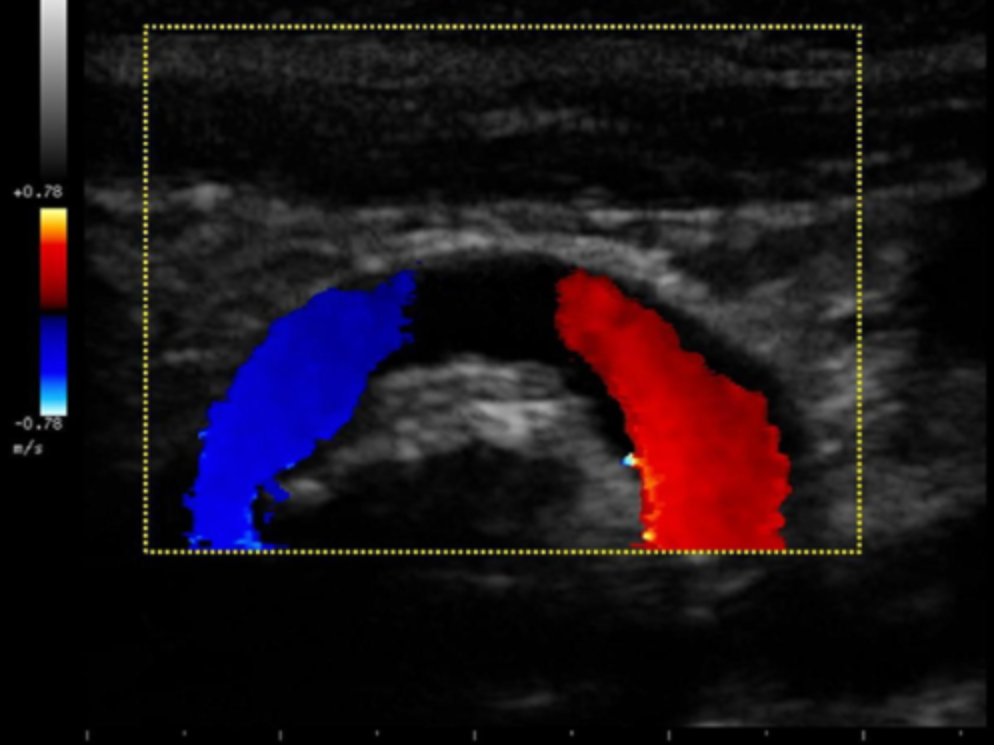

Which of the following statements best describes the reason why there is an absence of color flow in the vessel on the image?

a. The ultrasound beam is parallel to the motion of the blood so non flow is detected

b. the color Doppler gain is set too low to detect the slower flow at the curve in the vessel

c. there is an occlusion present. flow is demonstrated proximal to the lesion with collateral flow filling the distal portion of the vessel

d. the ultrasound beam is perpendicular to the motion of blood so no flow is detected

the ultrasound beam is perpendicular to the motion of blood so no flow is detected